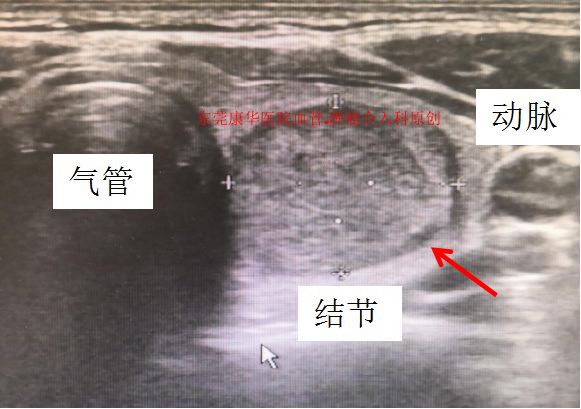

颈部巨大甲状腺结节压迫气管,使气管偏移

精确定位减少误伤,图为不到1cm的结节也能准确穿刺